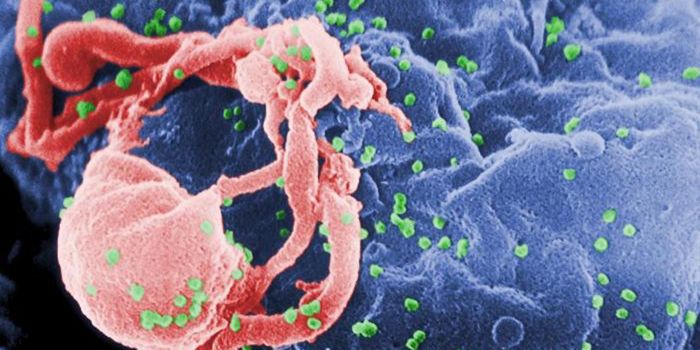

NOV 30, 2021ImmunologyHIV is a master of disguise. Once the virus enters the body, it has a number of sophisticated mechanisms through which i ...

NOV 22, 2021MicrobiologyThough treatments are available, there is no cure or vaccine from HIV, which impacts about 38 million people worldwide. ...

SEP 06, 2021MicrobiologyHIV vaccines have remained elusive in part because the virus has a powerful ability to mutate, and there are so many str ...

JUN 24, 2021ImmunologyA new study has revealed how stem cells can be used to amplify immune responses to HIV, the virus that causes AIDS. The ...